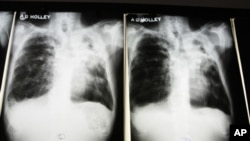

Novo tipo de tuberculose resiste a todos os medicamentos

A tuberculose (TB) ordinária é facilmente curada tomando antibióticos por seis a nove meses. No entanto, se o tratamento for interrompido ou a dose for cortada, as bactérias teimosas batalham e sofrem mutação para uma estirpe resistente que não pode mais ser morta pelos medicamentos padrão. A doença torna-se mais difícil e mais cara para o tratamento.